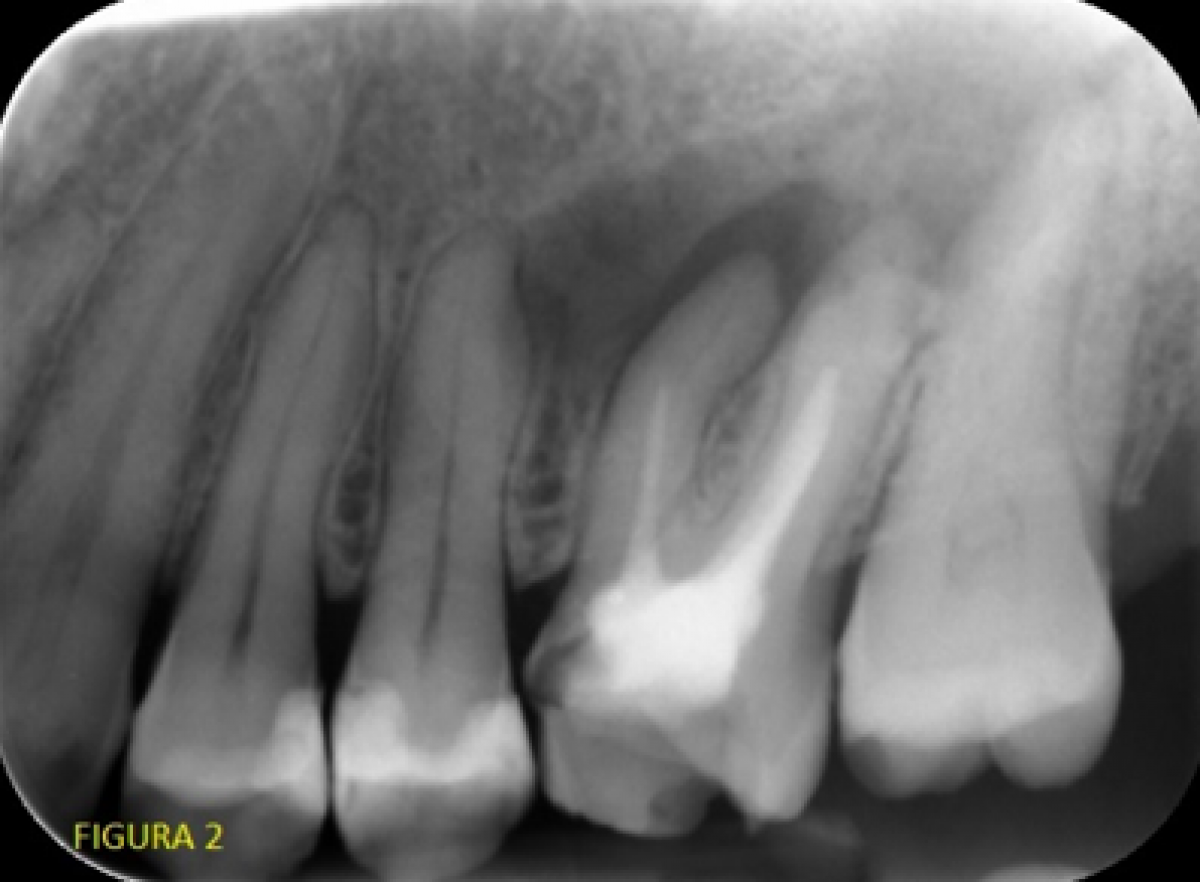

An intraoral X-ray revealed a clearly short root canal filling and a periapical radio-transparency of considerable size in zone 2.6 (Fig. 2).

After observing the CBCT performed 4 years earlier at a resolution of about 100 microns, we were able to state that the apical radio-transparency, while present, was smaller and that, unfortunately, it was impossible to obtain endodontic morphology information useful for facilitating treatment (Fig. 3).